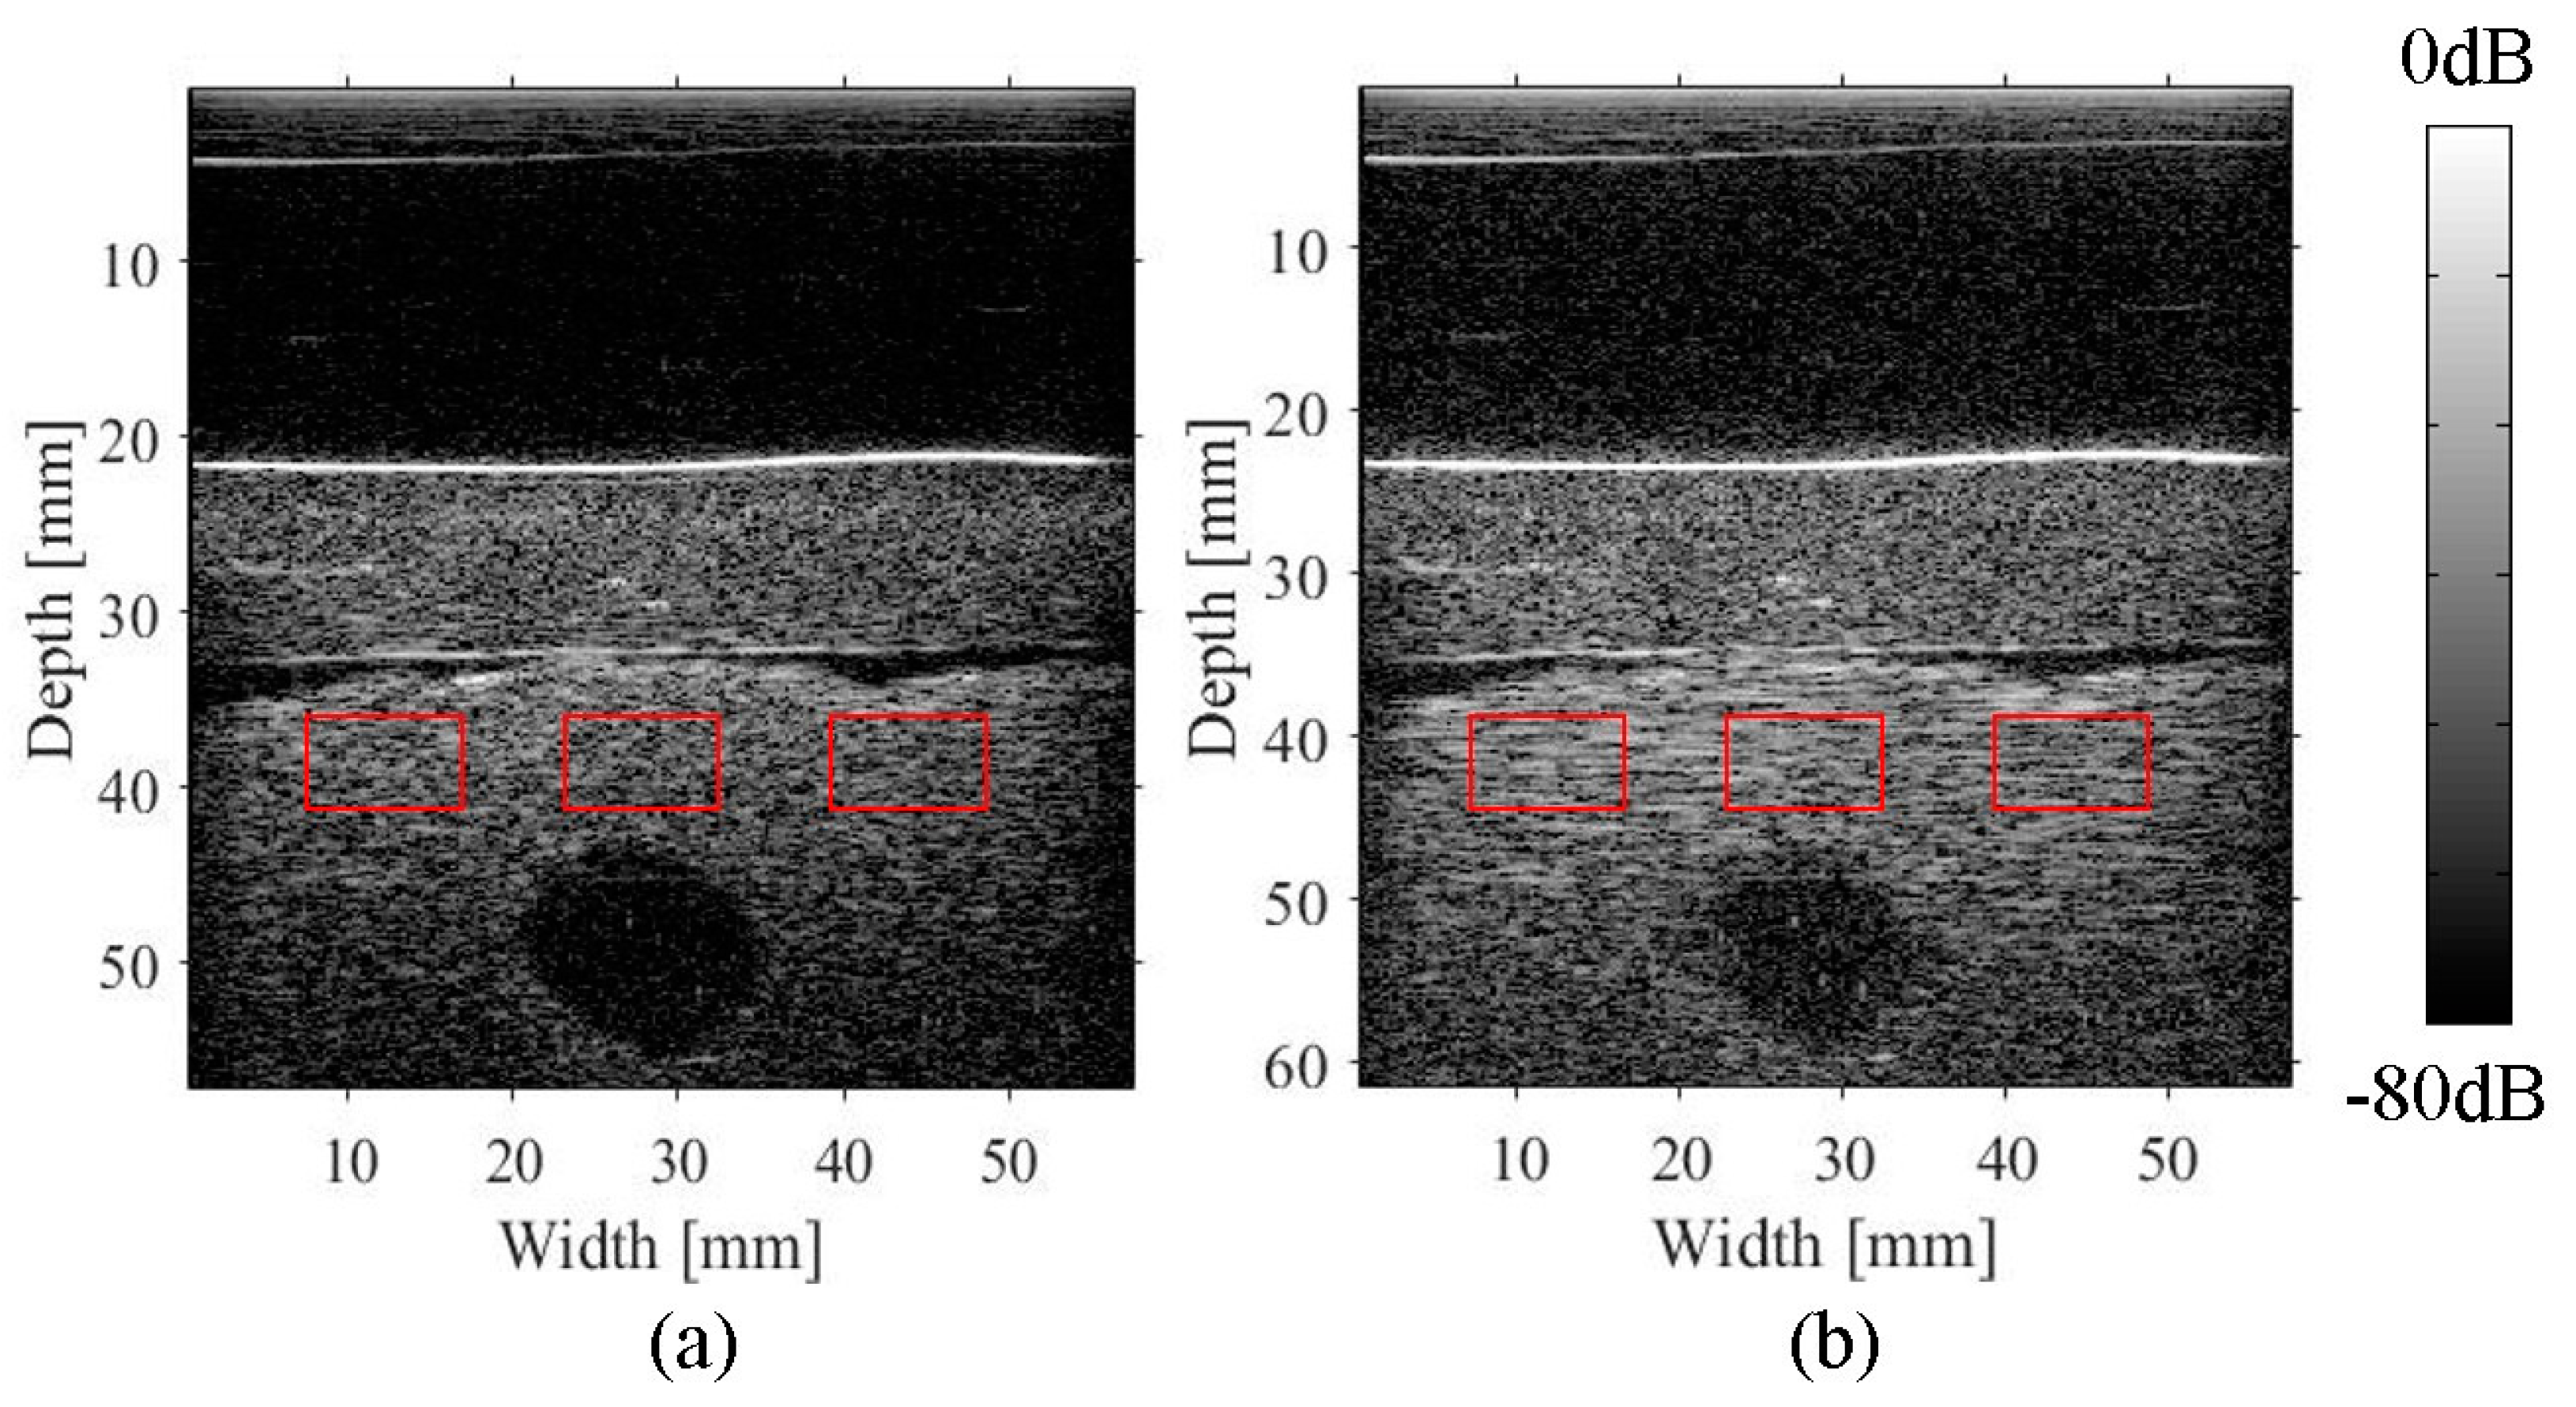

2.4. Experimental Imaging of an Abdominal Phantom using the Proposed Method of Compensating for the Sound Velocity Distribution to Correct Beamforming

3.2. Imaging of an Abdominal Phantom